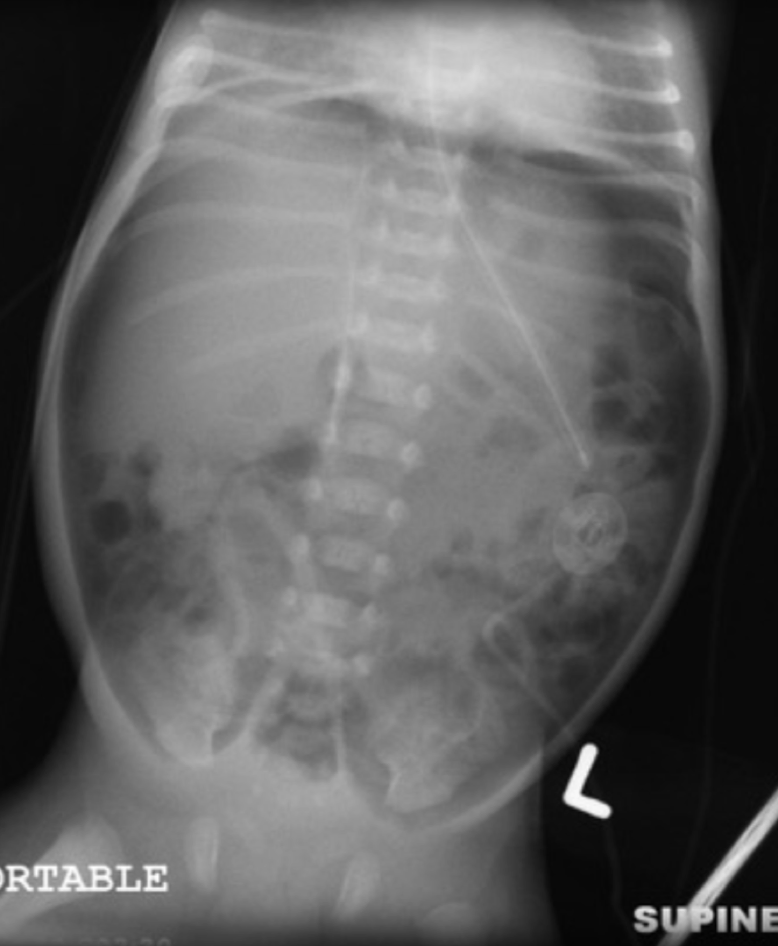

A baby w/ A/B episodes, metabolic and respiratory acidosis, pneumatosis intestinalis suddenly develops hypotension. What new finding might you see on KUB? that would suggest stage 3 NEC

pneumoperitoneum

what does a football sign mean on XR?

Seen with massive pneumoperitoneum

In supine position air collects anterior to abdominal viscera